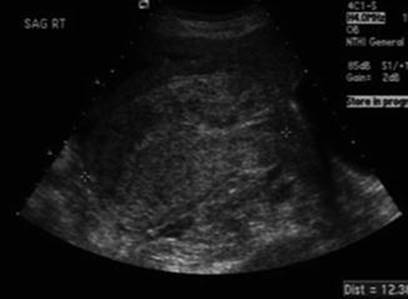

16.7.1 Transvaginal/Transabdominal Ultrasound

A transvaginal and transabdominal ultrasound should be performed to search direct and indirect findings of suspected uterine rupture. Direct signs are thinned wall with bulging of fetal parts (Fig. 16.6) or for visualization of the rupture. The fetus can be partly or completely out of the uterus (Fig. 16.7). Indirect signs are free peritoneal fluid (blood) especially in the pouch of Douglas, extraperitoneal hematoma, intrauterine blood, empty uterus, gestational sac above the uterus (Fig. 16.8), and large uterine mass with gas bubbles [183, 184, 207].

Fig. 16.7

Ultrasound image demonstrating contracted uterus (lower) with fetal extremities and amniotic sac outside the uterus [183]

Fig. 16.8

Ultrasound image demonstrating contracted uterus, endometrial stripe, and no intrauterine gestation, with the placental tissue above and bladder to the right [183]